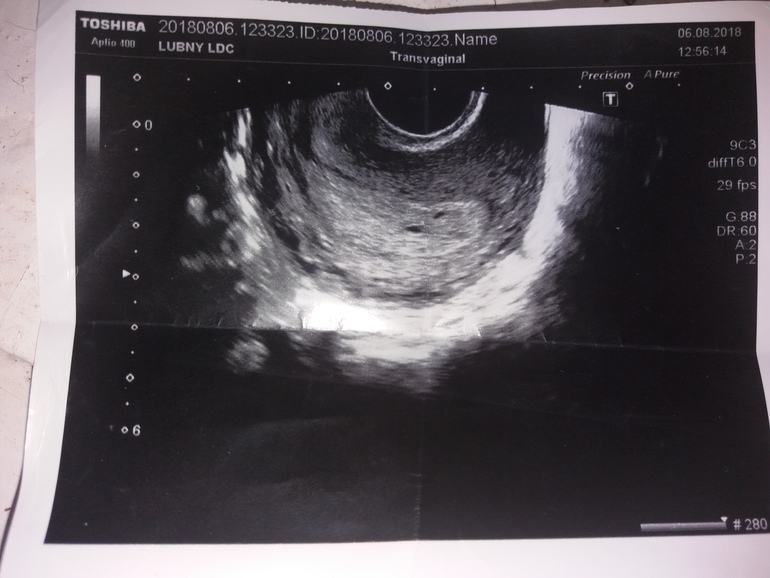

Вообщем ситуация такова, первый день последней менструации был 21 июня 2018, цыкл 31 день. Первый тест 3 августа(слабая вторая полоска).7 августа первый поход к гинекологу показал размер матки на 6 недель, УЗД в тот жэ день, показало 2 чёрные точки, которые узист воспринял как полипы и назначил повторное узд спустя неделю. 12 августа прошло второе УЗД, во время которого врач по внешнему осмотру не смог определить, а по внутреннему увидел беременность плодное яйцо или как там, 8мм и по сроку 5 недель и 5 дней, второй чёрной точки заметно не было. Живот по виду на этот срок не тянет, больше чем нужно...Может ли быть такое, что второй плод неважно сейчас? И возможно ли, что плодное яйцо меньших размеров из-за многослойной беременности? фото первого узд прилагаю